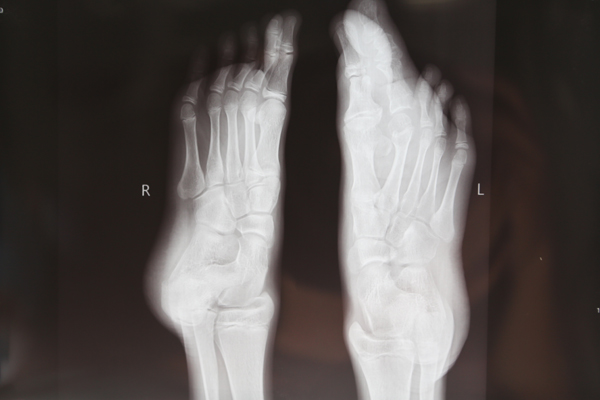

小东的父母带他找到了交大二院贺西京教授,经诊断,小东患的是一种罕见的巨趾(指)症。巨趾症是神经生长异常所致,以手指或足趾体积增大为特征的先天性畸形,在四肢先天性畸形中的发生率很低,约为0.9%。表现为某肢体软组织和骨组织均匀增大,体积为正常肢体体积的5倍。畸形生长给患者心理带来压力和痛苦,生活失去自信,严重影响患者的生活质量。贺教授接诊后,带领治疗小组仔细检查,研究小东的影像资料,制定慎密的手术治疗方案。确保功能,防止坏死,纠正外观… 于7月27日成功的为小东施行了巨指畸形矫正术。掰掉了左脚第二趾,重塑脚趾。解除了小东及其父母的烦恼。看着变得美观、好看的脚趾,小东开心的笑了。